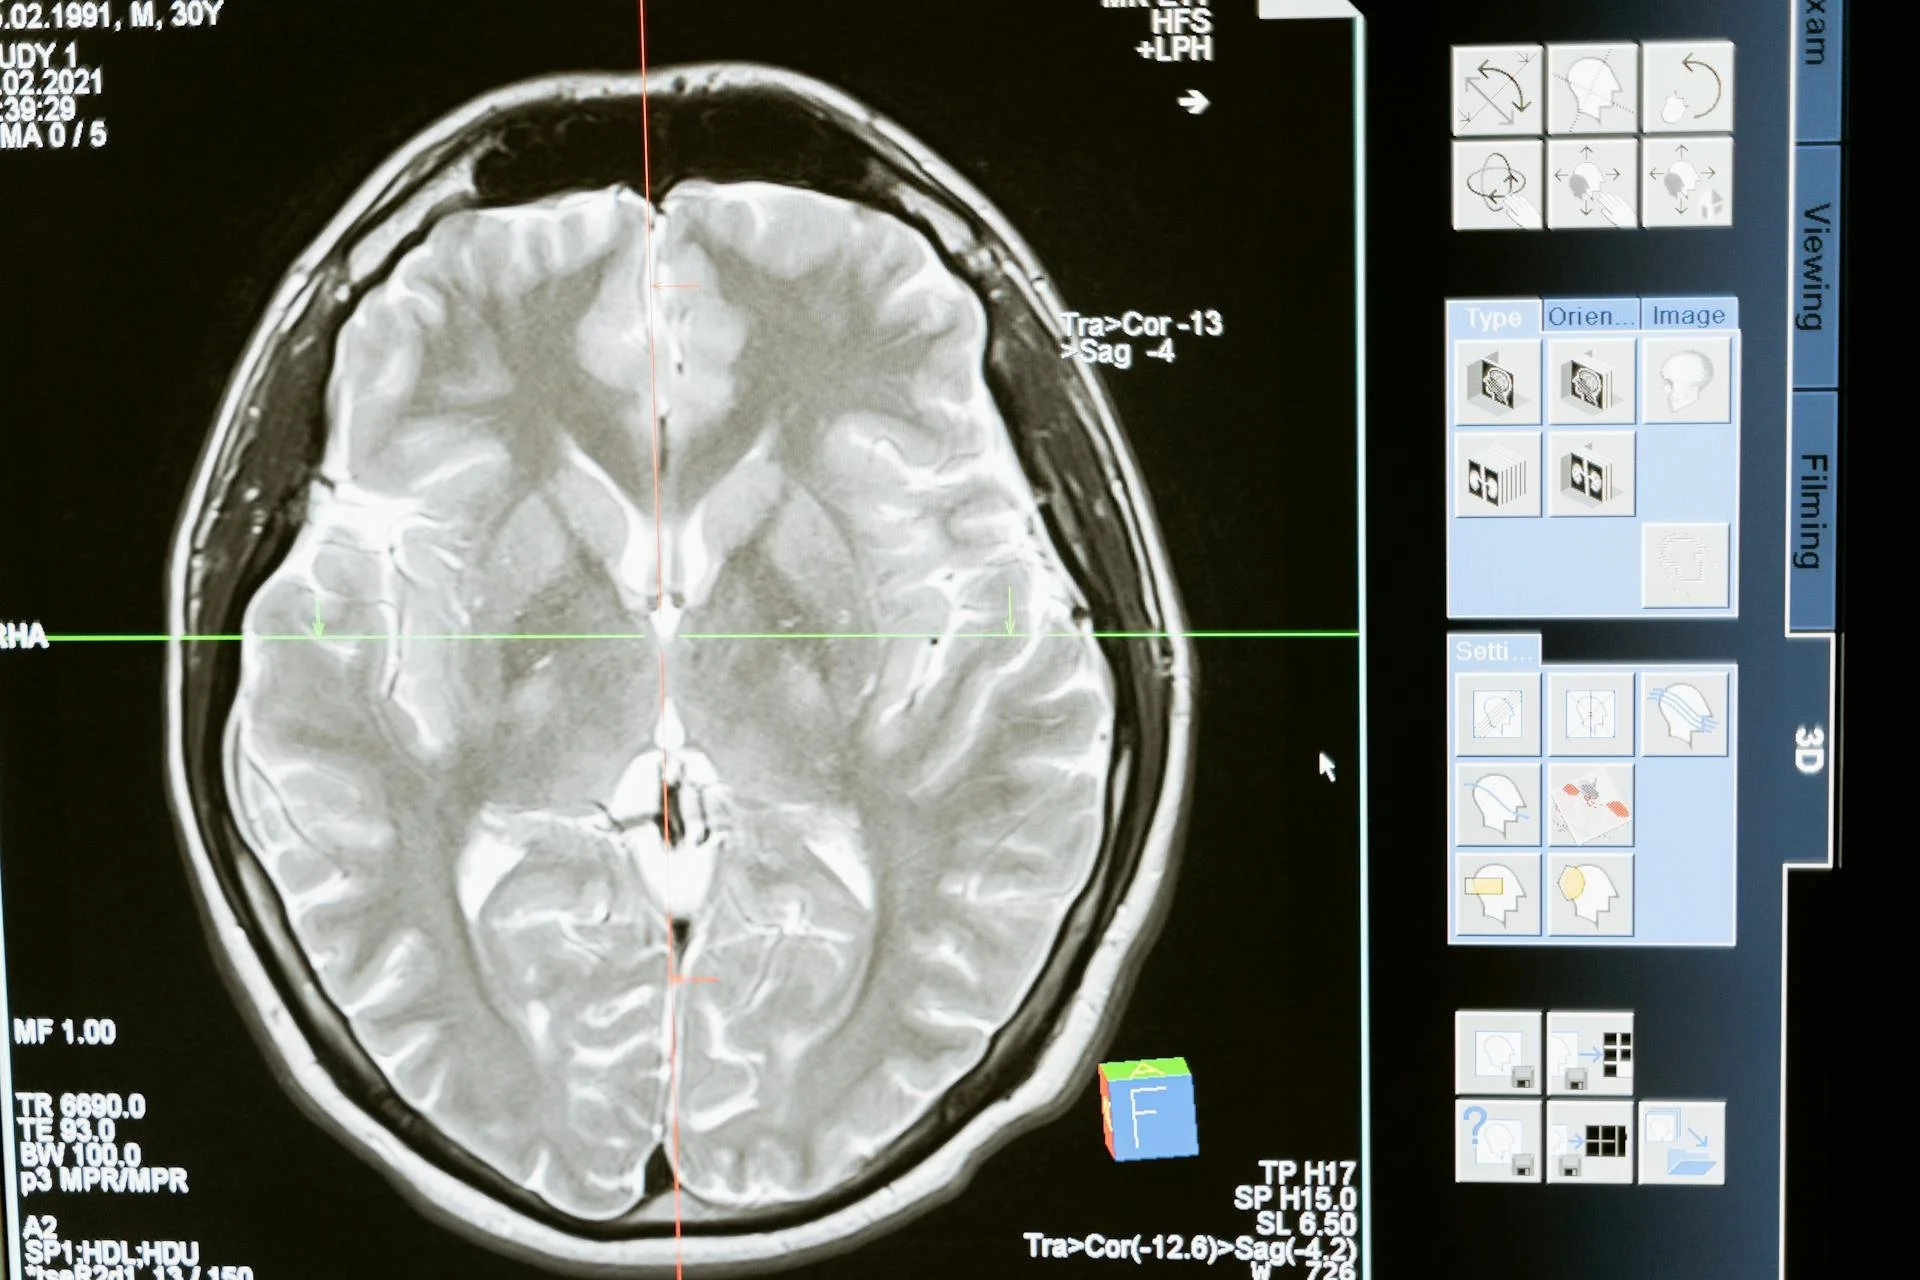

The brain is the centre controlling and managing the activities of the organs via nerve cells. Electric and chemical signals as well as hormonal molecules in glands and blood are the carriers of any information. For anything to become part of consciousness it must pass through the nervous system into the brain. It is in the higher regions of the brain where conscious experience arises.

It's easy to understand the different parts of the brain by dividing it into three major parts.